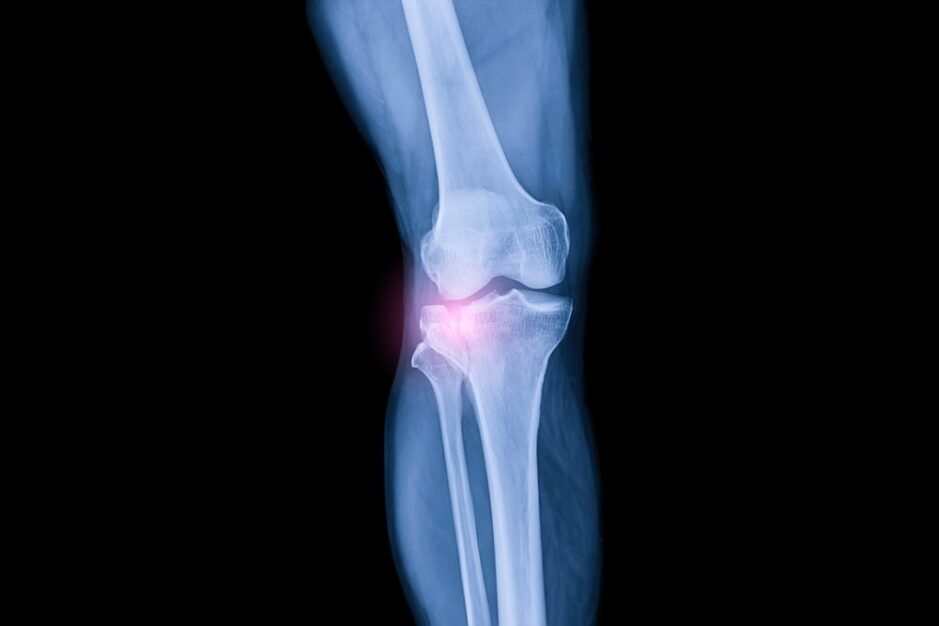

Одним из самых непосредственных преимуществ регенерации коленного хряща является значительное облегчение боли.

Воздействуя на симптоматические дефекты хряща и улучшая поврежденные участки сустава пациента, эта терапия восстанавливает более плавное движение в коленном суставе, улучшая подвижность и уменьшая дискомфорт, вызванный травмами суставов или повреждением хряща.